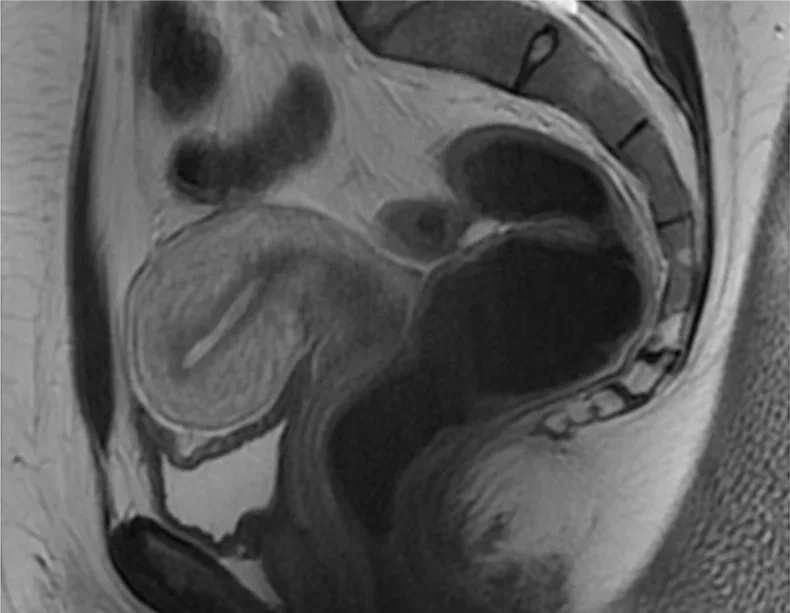

Figure 6.4. Cas témoin. Dysménorrhée primaire ; EVA : 2/10. Source : Dr Petit.

Dix cas témoins : dysménorrhée sans AS ni ménorragies ; score EVA ≤ 4/10.

Cas témoins : rien à signaler.